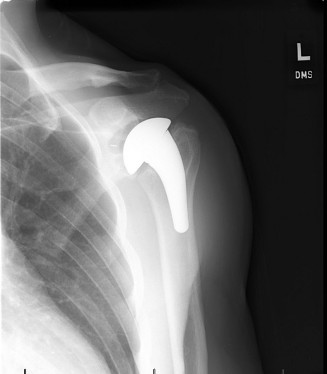

The correct answer is (E). Given that her rotator cuff has atrophied and has fatty infiltration to the point where there are equal parts fat and muscle, this is considered an irreparable rotator cuff tear. Repair should not be attempted because of poor outcomes following repair (see last two paragraphs of this discussion below). A reverse total shoulder arthroplasty is an alternative to repair that should be used in cases of massive, irreparable rotator cuff tears. It is a semi-constrained prosthesis that restores function in patients with massive rotator cuff tears by constraining a concave humeral cap inferior to a semispherical glenoid component (glenosphere). This creates an inferior force-couple and a fulcrum that replaces the stabilizing function of the infraspinatus maintaining a center of rotation around which the shoulder can move. This allows the deltoid to abduct and flex the shoulder without causing the humerus to migrate superiorly and about the acromion. In an elderly patient with a massive, irreparable rotator cuff tear (as in this patient), a reverse total shoulder arthroplasty is the procedure of choice.

It should be noted that reverse total shoulder arthroplasty is also the procedure of choice in patients with cuff-tear arthropathy (aka rotator cuff arthropathy). Characteristics of cuff-tear arthropathy include superior migration of the humerus due to a massive rotator cuff tear, glenohumeral joint destruction, subchondral osteoporosis, and humeral head collapse (see Fig. 2–17). A reverse total shoulder

arthroplasty in this case serves the purpose of eliminating pain caused by glenohumeral joint arthritis while restoring functional motion and is the procedure of choice in patients with cuff-tear arthropathy.

Figure 2–17_X-rays of a patient showing evidence of cuff tear arthropathy. The humerus is migrated superiorly, the glenohumeral joint is destroyed, there is subchondral osteoporosis, and the humeral head is collapsed. (From Ecklund KJ, Lee TQ, Tibone J, Gupta R. Rotator cuff tear arthropathy. _J Am Acad Orthop Surg. 2007;15(6):340–349.)